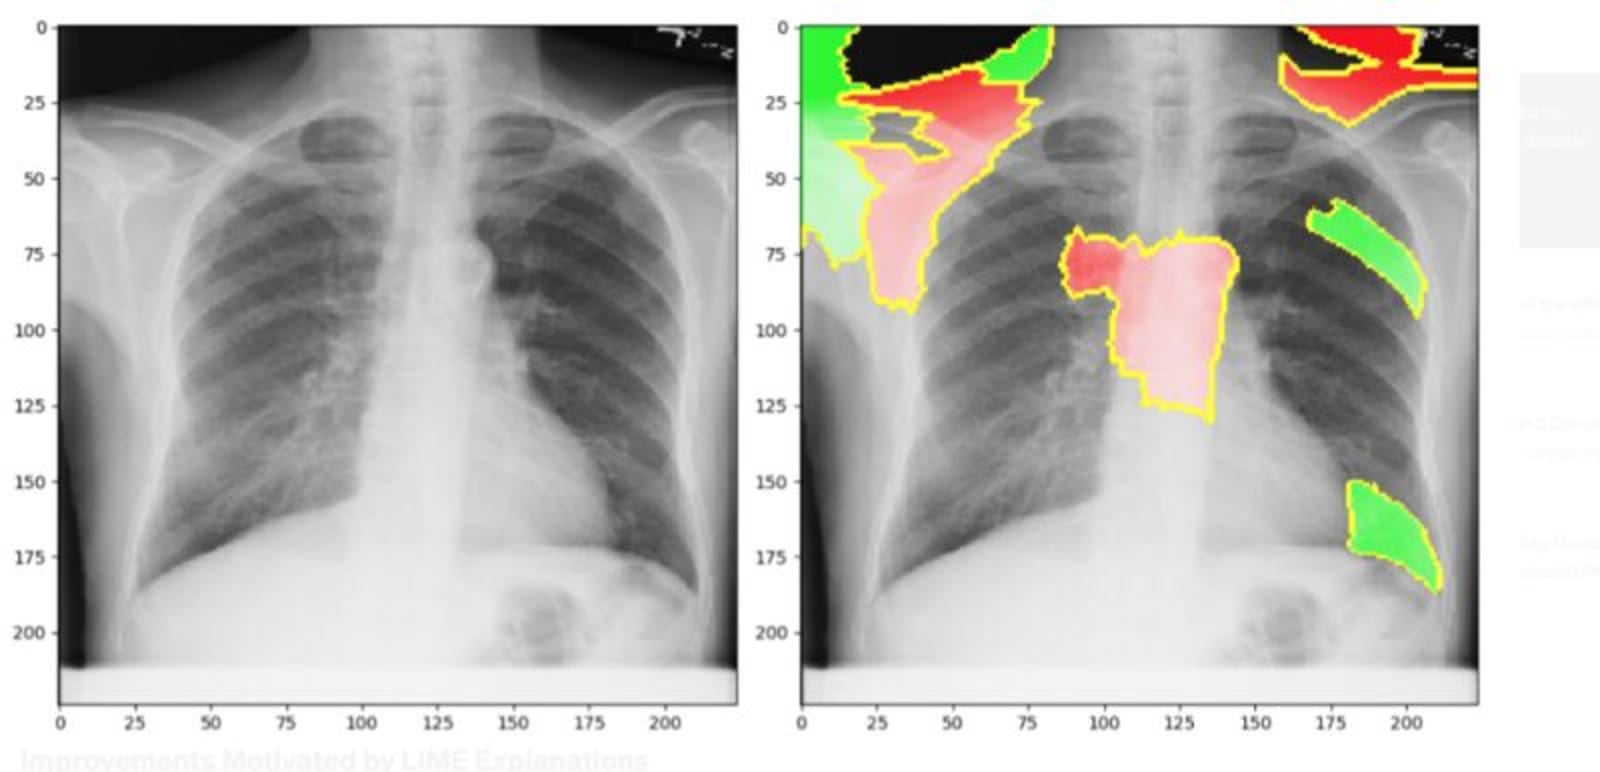

• Explaianle AI on X-Ray Chest Images for COVID-19 Patients

date: 2021

Organization:NRC

Description:

Worked with NRC, JRH hospital and the health community to combat COVID-19 in Canada by using my background knowledge in web designing and developing and utilizing Data science and explainable approaches to chest X-ray images.

A practical COVID-19 prediction and interpretation have been developed to assist the clinician in predicting the severity of the COVID-19 virus for each patient.

Impact: Implemented a web-based AI application to assist doctors in making better decisions for patients with COVID-19.

• Designed and developed a web-based clinical machine-learning application using Flask, React.js, HTML, and Python.

• Provided data preparation and data analytics on the Sepsis dataset collected by the clinics in Montreal.

• Implemented machine learning Explainability algorithm using Python, LIME and Dash

• Developed the machine learning explainability models